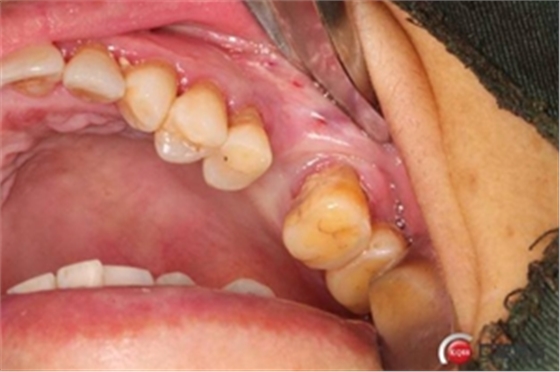

六個月之后